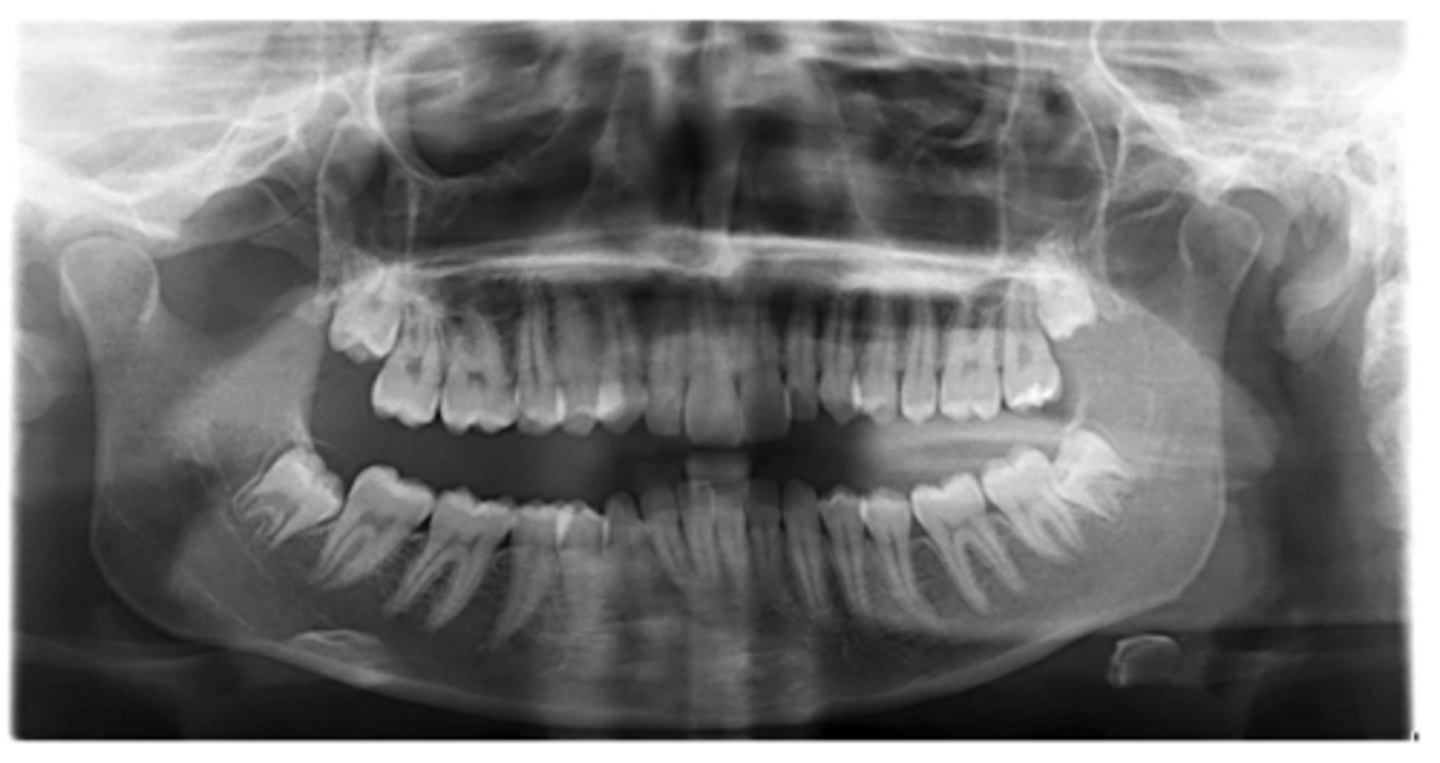

No

Are there congenitally missing teeth in the maxillary arch?

Are there congentially missing teeth in the mandibular arch?

Any supernumerary teeth?

Yes - mandibular second molars

Any impacted teeth?

Yes

Are the condyles symmetrical?

Maybe in the upper molars

Are there any dilacerated roots?

Are there congenitally missing teeth in the mandibular arch?

Are there any supernumerary teeth?

Are there retained primary teeth?

A little bit

Is there crowding?

Is there any pathology?

Possibly #20